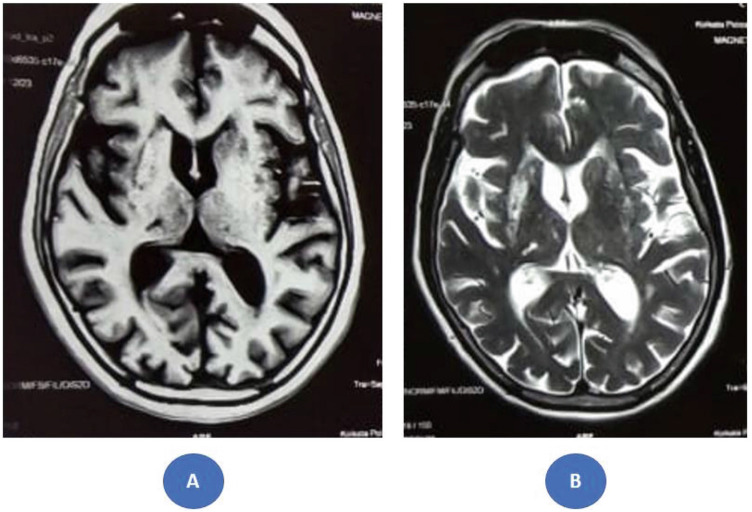

Case presentation: We present a case of DS in a 62-year-old woman from rural India with poorly controlled diabetes mellitus who developed acute-onset right hemichoreoballism. Neuroimaging revealed a predominantly right-sided striatal lesion, illustrating a clinicoradiological discordance-a mismatch between the clinical symptoms and radiological findings. Despite achieving tight glycemic control and administering neuroleptic medications, the involuntary movements demonstrated only partial improvement. Neurological changes persisted on the ipsilateral side of the affected limbs even after 1 year of follow-up. Notably, perioral dyskinesias developed during subsequent follow-up visits.